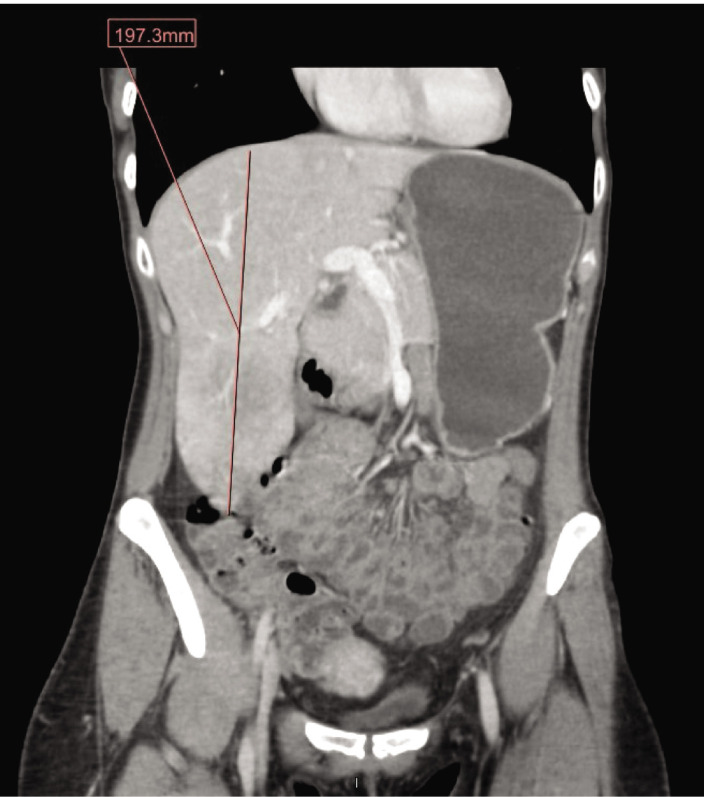

Riedel's lobe of the liver is a rare anatomical variant often incidentally found on imaging or through the presence of hepatomegaly on physical examination. While patients are usually asymptomatic, the presentation of this condition can vary, ranging from nonspecific symptoms to more severe issues such as torsion, obstruction, rupture, and bleeding. We present a case of a patient with asymptomatic hepatomegaly who was incidentally found to have Riedel's lobe of the liver, accompanied by an elevated IgG mitochondrial antibody. The range of symptoms associated with this rare anatomical variation underscores its importance in diagnosis and surveillance within this patient population.

Abstract Image